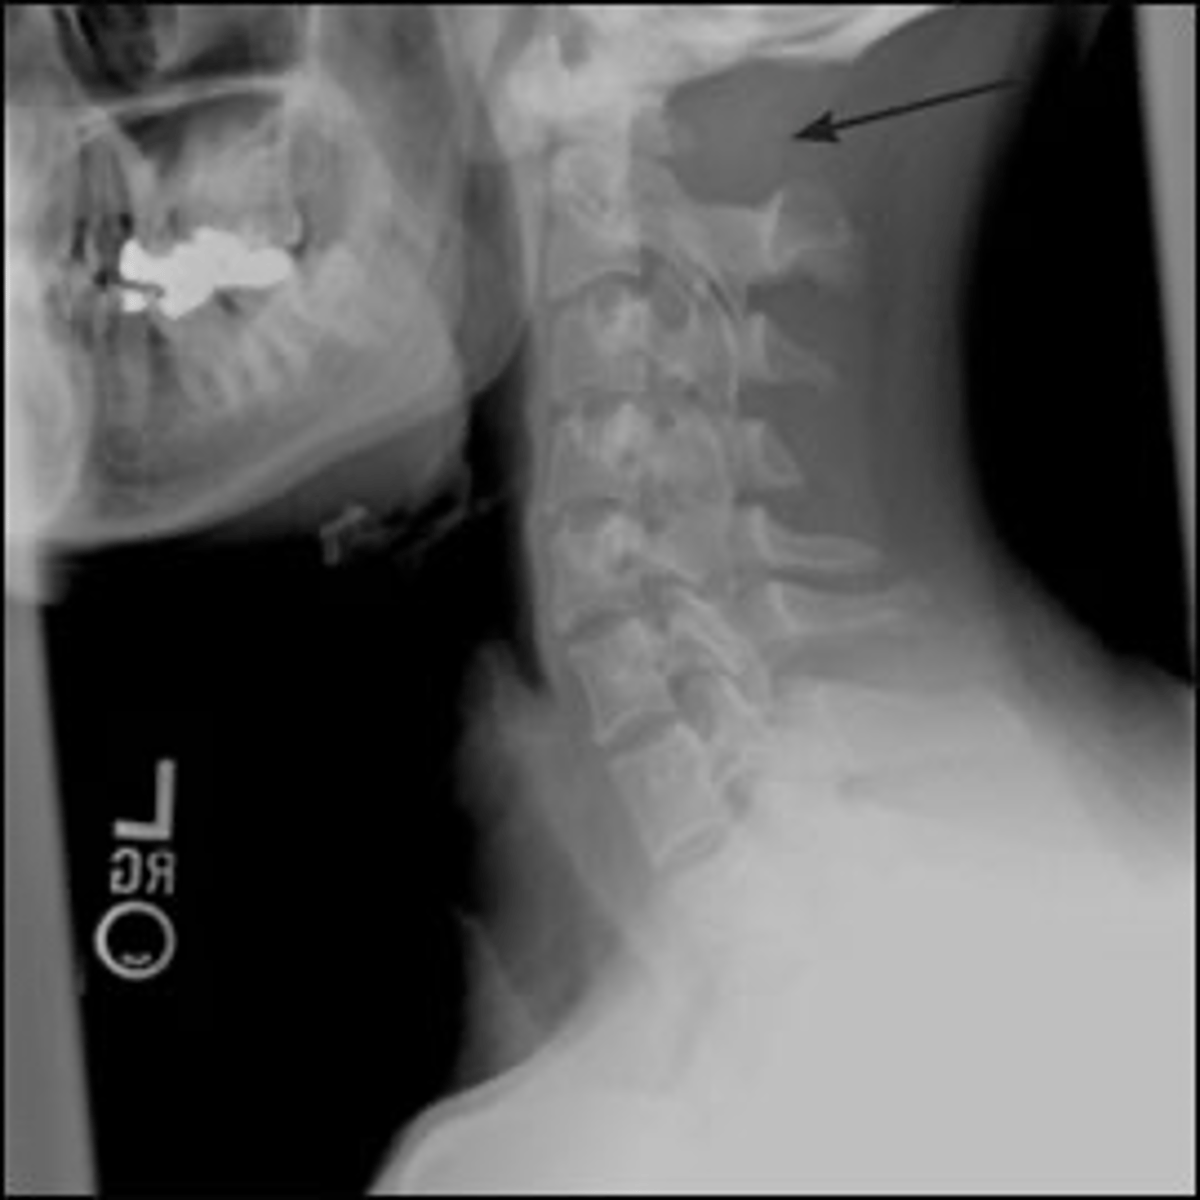

Vignette # 2

Sex: Male

Age: 23

Chief Complaint: Football player presents with nausea after being hit from behind. He reports feeling dizzy when he is stretching his neck.

1. What are your differential diagnoses? (Choose 3)

a. Dens fracture

b. Hangman's fracture

c. Os odontoideum

d. Teardrop fracture

e. Whiplash

f. Facet dislocation

g. Jefferson Burst Fracture

h. Brown Sequard